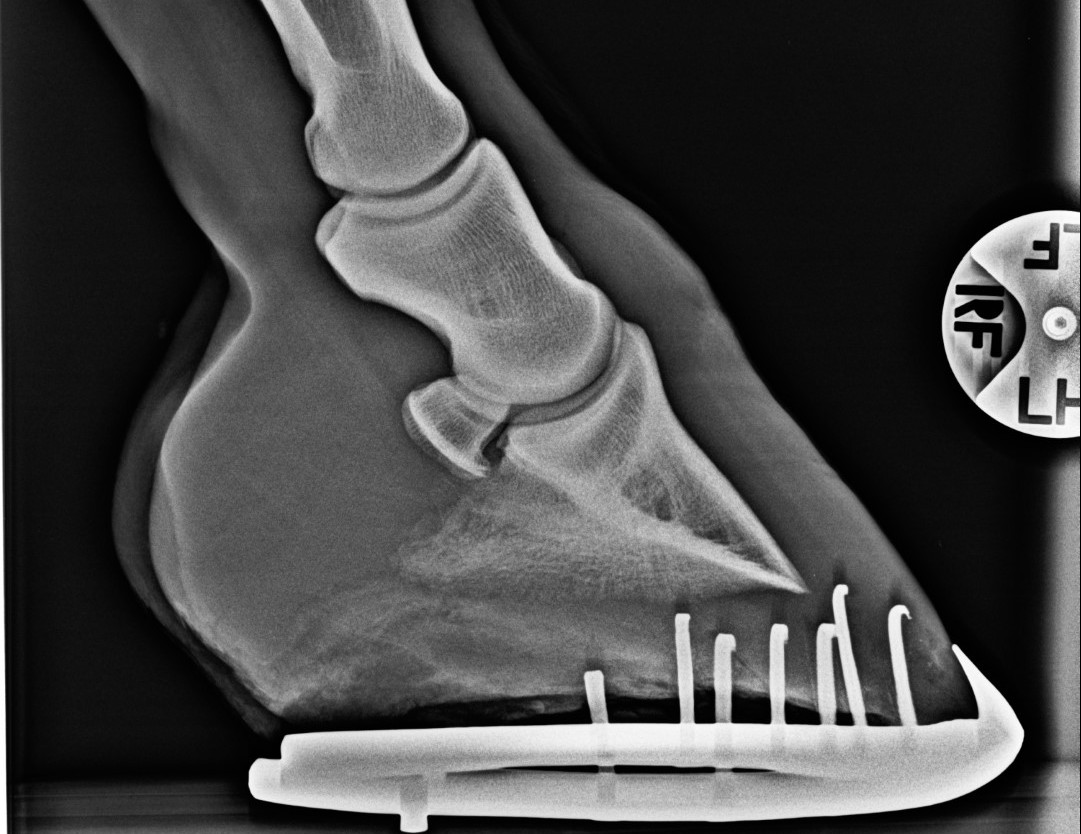

A harmadik fő alkalmazása a röntgennek a lábvég belső viszonyainak vizsgálata a megfelelő körmölés, patkolás kivitelezéséhez. Szerencsére egyre többször készítünk felvételeket azért, hogy a patkolókováccsal közösen megbeszélve a legjobb módon lehessen a lovat körmölni, patkolni.